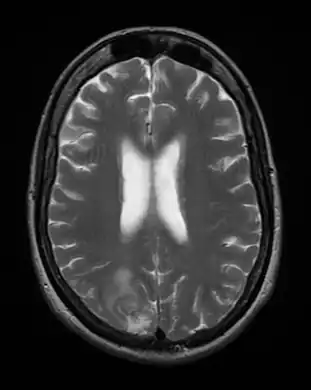

Cerebral toxoplasmosis -

Cerebral toxoplasmosis